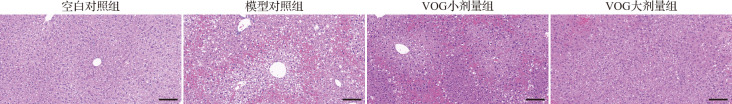

Methods: C57BL/6 mice were randomly divided into 4 groups: normal control group, model control group, low-dose group of VOG (30 mg/kg), and high-dose group of VOG (60 mg/kg). Acute liver injury was induced by intraperitoneal injection of acetaminophen (500 mg/kg). VOG was administrated by gavage 2 h before acetaminophen treatment in VOG groups. The protective effect of VOG against acute liver injury was evaluated by detecting alanine transaminase (ALT), aspartate transaminase (AST) levels and hematoxylin and eosin staining. The malondialdehyde (MDA) content, superoxide dismutase (SOD) and catalase (CAT) activity in liver were detected to evaluate the hepatic oxidative stress. The expression levels of tumor necrosis factor (TNF)-α, Il-, and Il-6 in liver were detected by quantitative reverse transcription polymerase chain reaction (qRT-PCR). The expression levels of phosphorylated c-jun N-terminal kinase (JNK)/JNK, phosphorylated p38/p38, inositol-requiring enzyme 1 alpha (IRE-1α), X-box binding protein 1s (XBP1s), and glucose-regulated protein 78 (GRP78) in liver were detected by Western blotting. An endoplasmic reticulum stress model was established in AML-12 cells using tunicamycin. Cell viability was assessed using the CCK-8 assay, and the degree of cell damage was detected by lactate dehydrogenase (LDH) assay. The gene expression levels of Ire-, Xbp1s, and Grp78 in the cells were detected using qRT-PCR.

Results: In the animal experiments, compared with the model control group, VOG significantly improved plasma ALT and AST levels, liver MDA content, as well as SOD and CAT activities. VOG also reduced the expression levels of Tnf-α, Il-, and Il-6 in the liver, and improved protein phosphorylation levels of JNK and p38, as well as the protein expression levels of IRE-1α, XBP1s, and GRP78. In cell experiments, VOG pretreatment enhanced cell viability, reduced LDH release and decreased the mRNA expression of Ire-, Xbp1s, and Grp78.